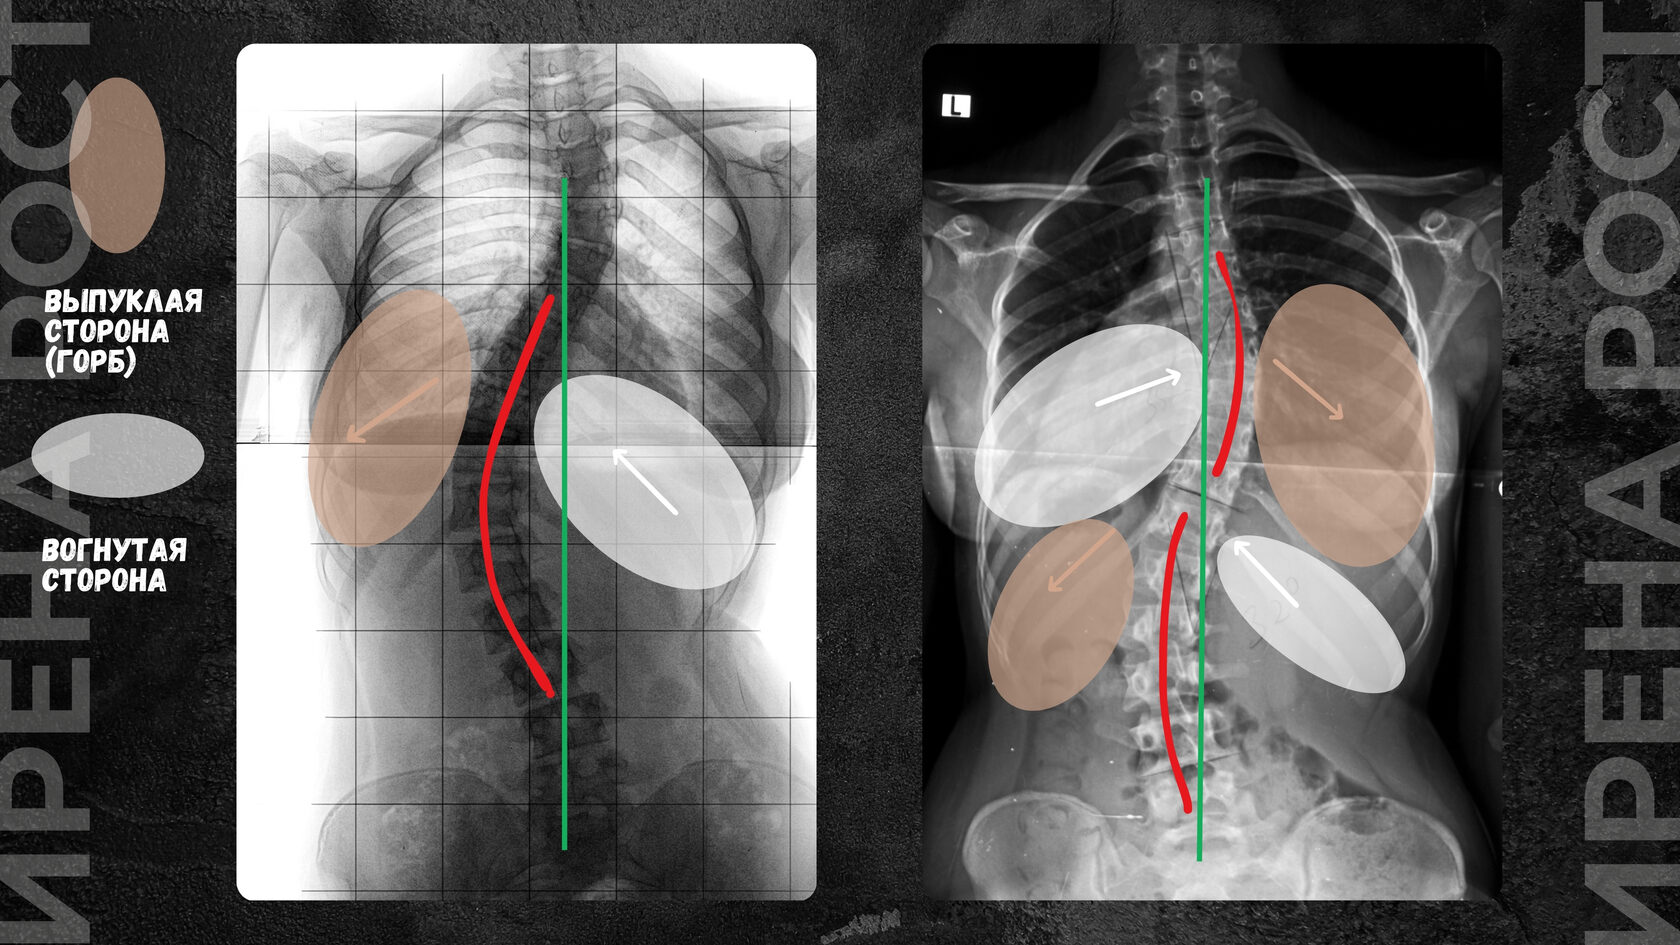

Так, со стороны сколиотической дуги ребра начинают сжиматься, создавая выпуклость полости грудной клетки, создавая реберное выпячивание (горб), а со стороны, противоположной дуге, ребра, наоборот, растягиваются, создавая сплющенность (впуклость) грудной клетки.

Представьте воздушный шарик, который с одной стороны сплющивают вертикально, а с другой - горизонтально, и вы схематично поймете, как меняется объем полостей грудной клетки при ее вовлечении в сколиотическую дугу.